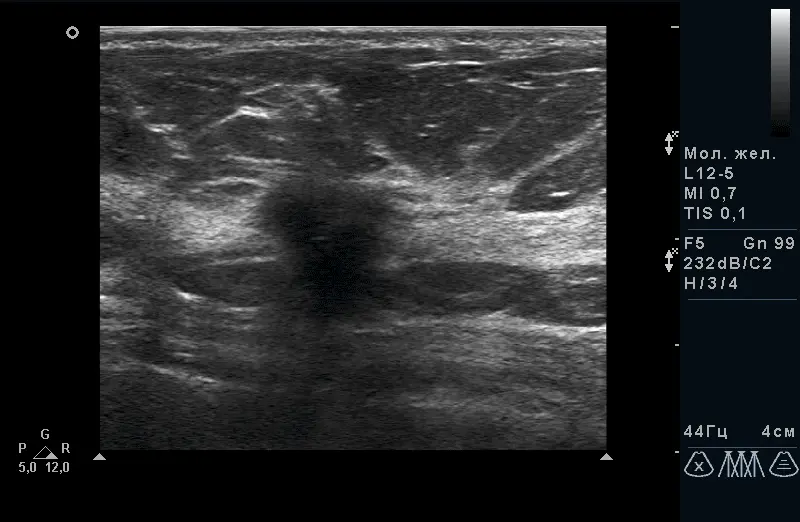

Рис.2. Дифузна форма мастопатії без гіперплазії і фіброзу. |